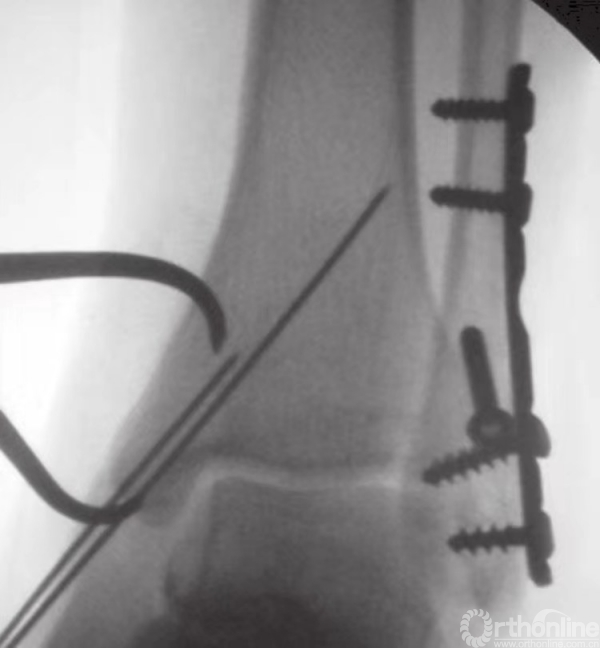

在钳的前方和后方,放置两枚较小的克氏针,并使之与骨折线垂直(图15)。注意要保证克氏针不刺穿踝关节(图16)。为防止刺穿关节,可将角度调至与水平方向约成30°。在克氏针上方和对侧皮质附近,使用管状钻钻孔。后嵌入4mm部分有螺纹的空心松质骨螺钉。

图15 2枚克氏针临时固定骨折

图16 透视下观察克氏针方位及骨折复位情况